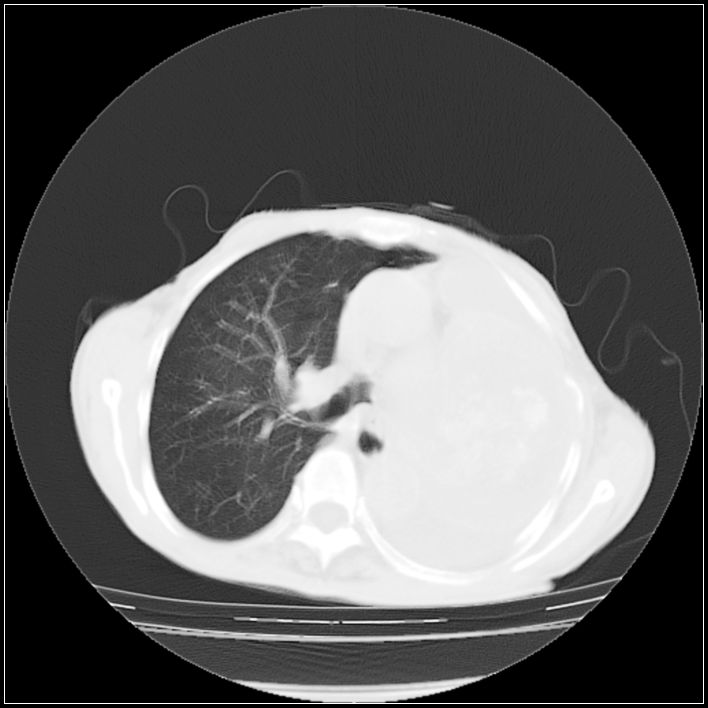

以下是引用ydx_74在2008-5-31 16:08:00的发言:[br]中心性肺癌并左侧肺不张、胸水。

以下是引用影象小辈在2008-5-31 16:25:00的发言:[br]左侧胸腔团状不规则致密影,界欠规整,密度不均匀,其内可见更低密度影及高密度影,并可见包裹性胸腔积液 考虑为1.畸胎瘤 2.肺癌